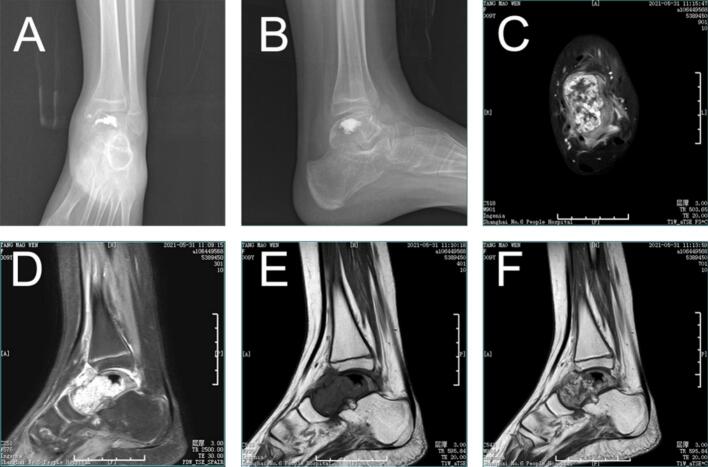

Postoperative pathology results were consistent with the findings from the initial puncture pathology. The wound healed well, and the ankle joint was immobilized in plaster for six weeks. During this time, we asked the patient to keep the leg elevated to reduce swelling. After 6 weeks, the cast was removed and partial weight-bearing exercise was gradually started under the guidance of a physical therapist. The physical therapist also provided instructions regarding range of motion exercises to improve ankle flexibility. The physical therapy program consisted of a progressive program. In the initial stage, gentle range of motion exercises, including ankle dorsiflexion, plantarflexion, varus, and valgus, were performed after removal of the cast. As the patient improved, resistance exercises were added to strengthen the ankle muscles. These movements include the use of elastic bands and a heel lift. Balance training is also an important part of the program, with patients standing on one leg and performing various balance tasks. The physical therapist adjusts the intensity and frequency of exercise according to the patient's progress and tolerance. At 12 weeks after surgery, the patient was allowed to bear full weight and continued a home exercise program to maintain and improve ankle function. Three months following the operation, the child was able to walk independently. Ankle function was assessed at six months (Fig. 5) and thirteen months (Fig. 6) postoperatively, with the AOFAS score improving from 75 to 91, thereby adequately meeting the requirements for daily activities. Weight-bearing ankle radiographs indicated that the prosthesis was well-positioned in relation to the contralateral joint. The range of motion of the ankle joint in the directions of plantarflexion, varus and valgus were measured during the follow-up, and the range of motion of the ankle joint was compared with that of normal children. The results showed that the range of motion of the ankle joint gradually improved with time, and it was close to the normal range at 13 months after operation, which further proved the effectiveness of the surgical method. At 3 years after operation (Fig. 7), the X-ray films of the ankle joint showed good position and stable prosthesis. The ankle function score was similar to the previous one, and there was no obvious ankle instability and pain after walking. The distal tibial articular surface of the patient was effectively protected without obvious bone destruction. Compared with the initial operation, the epiphysis of the patient had developed normally and no leg length discrepancy occurred, which also met our preoperative expectation and established a good foundation for the subsequent ankle revision surgery.

Fig. 5.

X-ray evaluation 6 months after surgery. (A)bilateral anteroposterior radiographs. (B,E)bilateral non-weight-bearing lateral radiographs. (C,F)bilateral weight-bearing lateral radiographs. (D)bilateral axial radiographs of calcaneus

Fig. 6.

Preoperative and postoperative photos. (A,B) before surgery. (C,D)6 months after surgery. (E,F) X-ray evaluation after surgery.13 months after surgery

Fig. 7.

The X-ray films were reviewed 3 years after operation. (A) Lateral radiographs. (B) anteroposterior radiographs.